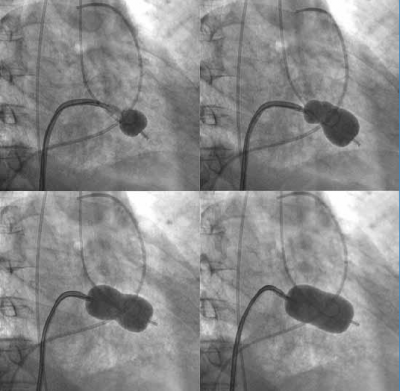

PTMC(僧帽弁交連裂開術)の実際

1. 足の付け根の静脈からカテーテルを挿入していきます

2. 右心房から左心房にカテーテルを通します

3. イノウエバルーンを僧帽弁に押し当てて拡張し弁交連を裂開し拡張します

4. カテーテルを抜いて止血を行います

手術時間は約60-90分です。手術当日夕食から食事可能、治療後1-2日で退院可能です。